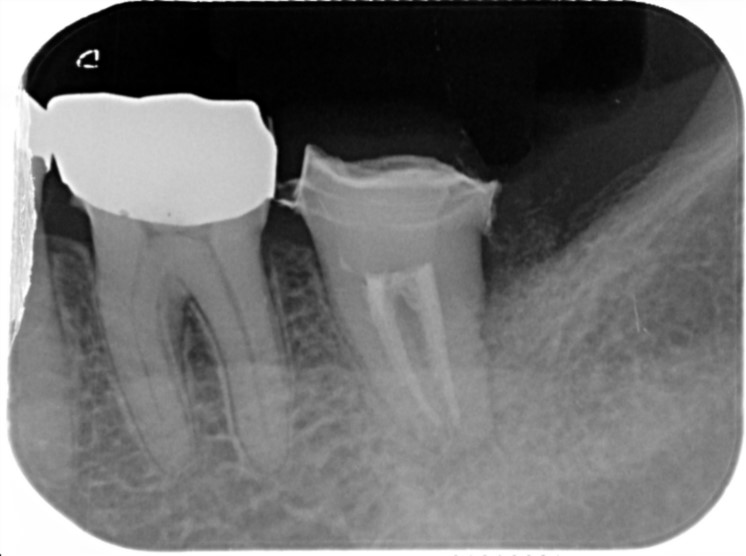

他院で作成された被せ物をやり替えた際にお痛みがあり、再度治療を始めたがこれ以上の治療はできないと言われてしまい治療中断。

悩まれた末に当院にご来院くださりお話をお聞きしました。

1つの根っこにひびが入っていることなどがわかりましたが抜歯ではなく、できるだけ歯を残存させることを目的とした治療計画を立てて根っこの治療を開始しました。

ひびが入っている根っこがあることがわかります。

12/3

ひびが入っていた根っこ以外を利用してできるだけ抜歯を避けました。

10/15

見た目も違和感なく被せ物をかぶせることができました。

治療部位 | 右下6番 |

費用 | 約100000円 |

治療期間 | 9ヶ月 |